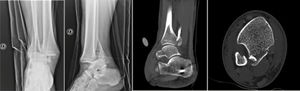

Caso 2El segundo caso que reportamos es de un paciente de sexo masculino de 24 años, sano y sin antecedentes mórbidos, que sufre un mecanismo torsional tipo supinación asociada a rotación externa de su tobillo derecho al bajar una rampa. Ingresa al servicio de urgencias con deformidad evidente, impotencia funcional, edema moderado, sin lesiones en piel y estado neurovascular distal conservado. Se solicitan y toman radiografías (figura 4), diagnosticando una luxofractura trimaleolar del tobillo derecho. En primera instancia se intenta la reducción cerrada la cual resulta insatisfactoria por lo que ingresa a pabellón para reducción cerrada e instalación de un fijador externo en configuración delta.

Radiografías y tomografía computarizada de luxofractura de Bosworth. A y B: radiografía de tobillo en proyección AP y lateral, respectivamente, donde se evidencia luxofractura trimaleolar. C y D: tomografía computarizada en cortes sagital y axial, respectivamente, donde se observa fragmento proximal de fíbula interpuesto en foco de fractura de maléolo posterior.

Durante las primeras 24 horas de la lesión, se diagnostica la luxofractura de Bosworth sospechando la lesión en las radiografías ortogonales del tobillo (figura 4) y se confirma con la realización de una TC la presencia de una luxación tibio-fibular distal con atrapamiento del fragmento proximal de la fíbula en el rasgo de fractura del maléolo posterior (figura 4).